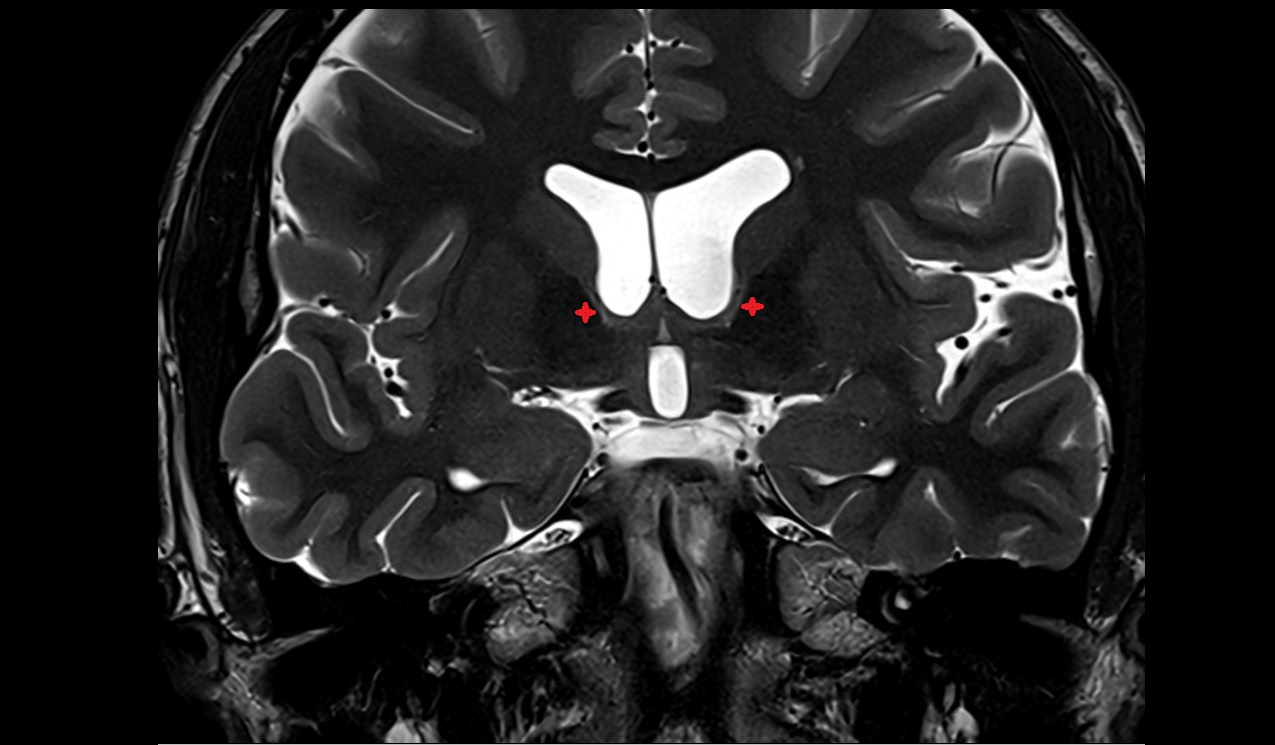

- Thalamus

- Head of caudate nucleus

- Putamen